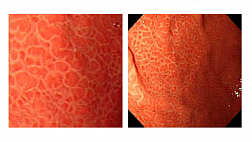

Вы выполняете, приближенное к реальности, обследование бронхиального дерева в HDTV качестве бронхоскопом BF-H190.

Реализована функция внутрипросветной эндонавигации по бронхиальному дереву!

Вы сможете последовательно начиная от карины, используя тачскрин, выбирать направление и изучать\вспоминать анатомию бронхиального дерев

Комментарии диктора статичных изображений и переходные видео применены для максимального облегчения пространственной ориентации и подробного объяснения о ангуляции и движении бронхоскопа во время исследования.ВИДЕО работы приложения можно посмотреть на сайте разработчика:

You are welcome to experience a bronchoscopic examination, almost as if it were done in a real clinical setting. Starting at the main carina, this app enables you to steer a HDTV bronchoscope through the bronchial tree step-by-step, from one carina to the next. Audio commentated still images and transitional videos are displayed facilitating spatial orientation and providing detailed explanation about the angulation and movement of the bronchoscope. Highly experienced medical experts have been involved in the development of this training app; however, please keep the following aspects in mind: